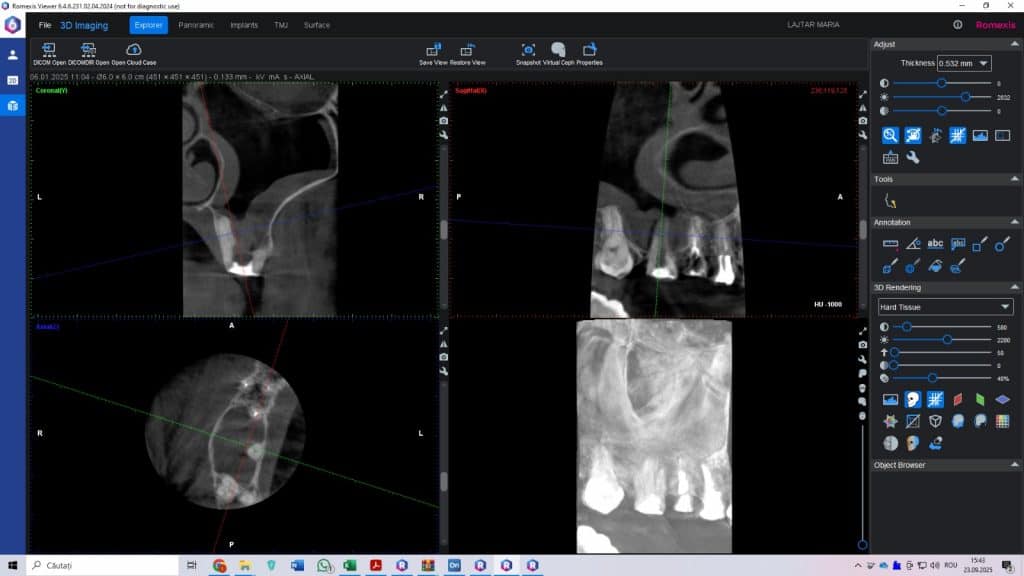

Fig. 2. CBCT la 9 luni – dintele salvat și sinus vindecat

Care a fost rezultatul?

• dintele a fost salvat

• infecția a dispărut

• sinusul maxilar s-a vindecat

• pacienta nu a mai avut dureri

• la controlul de 9 luni, dintele era stabil și funcțional